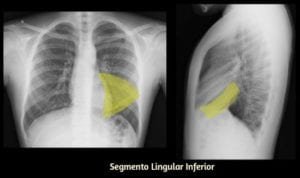

Início/Você Descreve Corretamente a Localização das Imagens Pulmonares nos Exames Radiológicos?/raiox do pulmao 18 raiox do pulmao 18